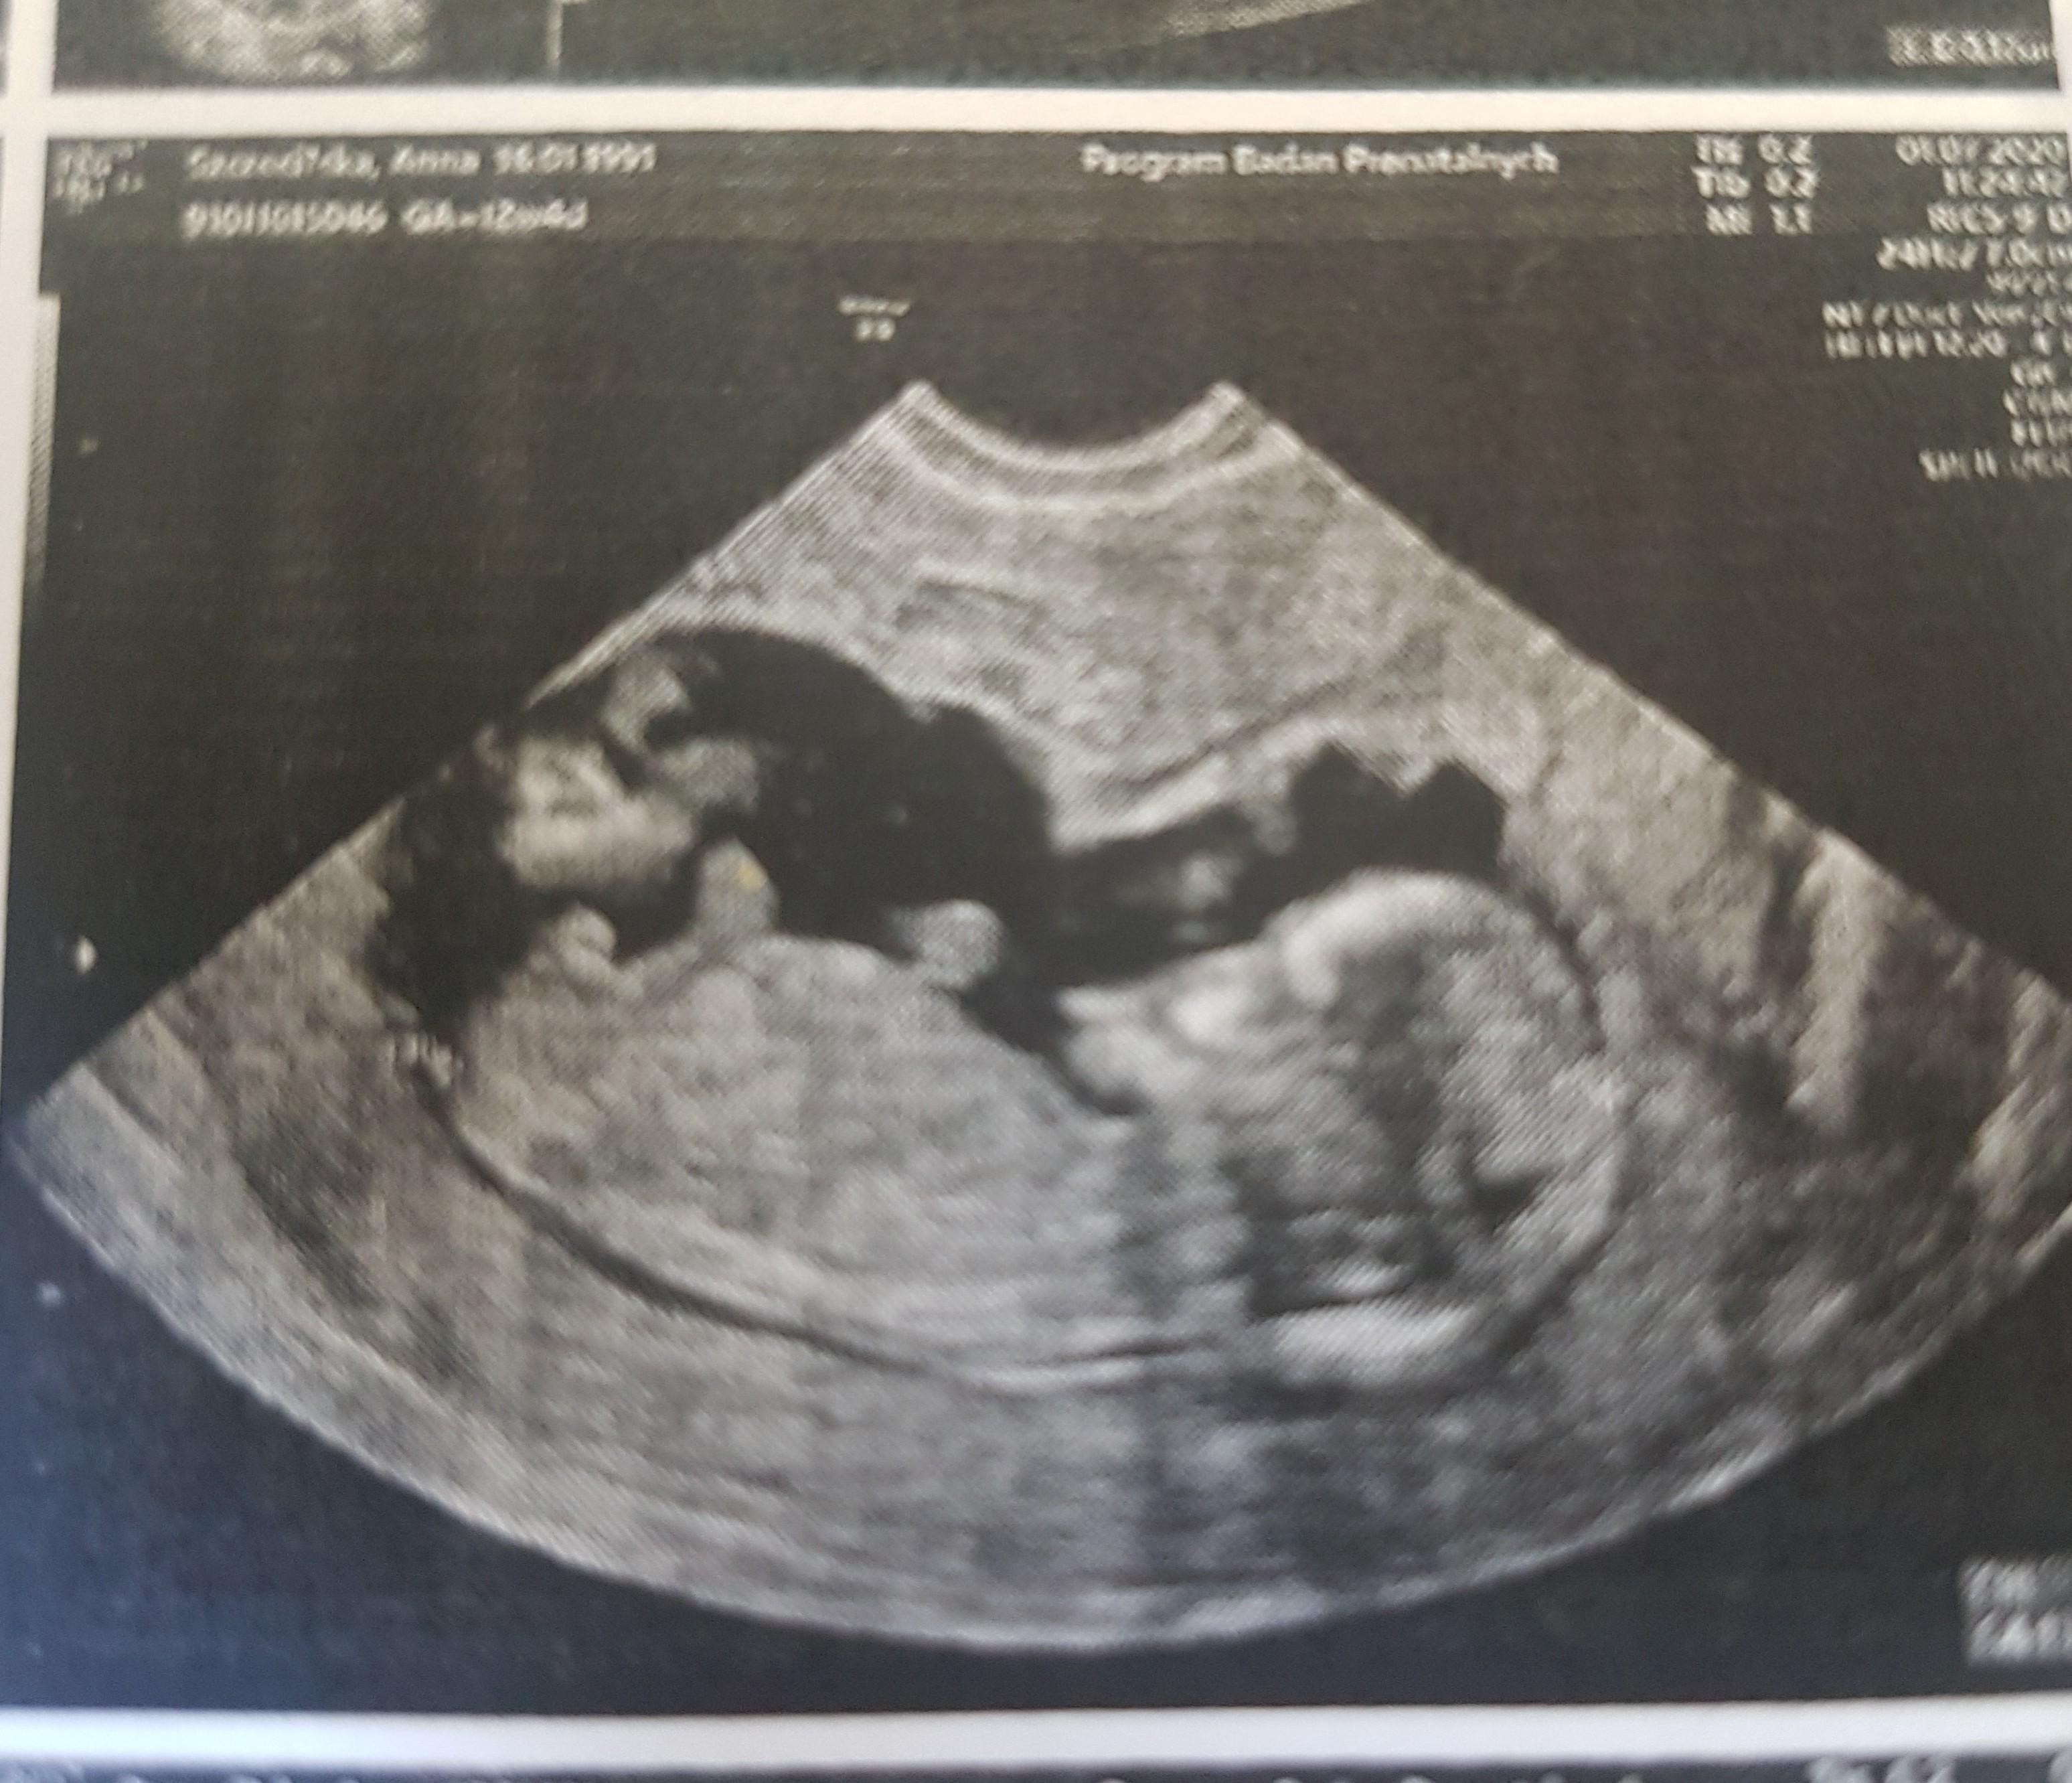

To juz brzmi zdecydowanie lepiej! Bądź dobrej myśli [emoji3590][emoji3059]Lekarz mówił prosze się nie denerwować to sa statystyki . Z usg nie widać zeby coś było nie tak. Wszystkie wymiary są ok , przelywy również ale białko niestety złe. Będę brać ten acard 150

I będę miala Synka![]()